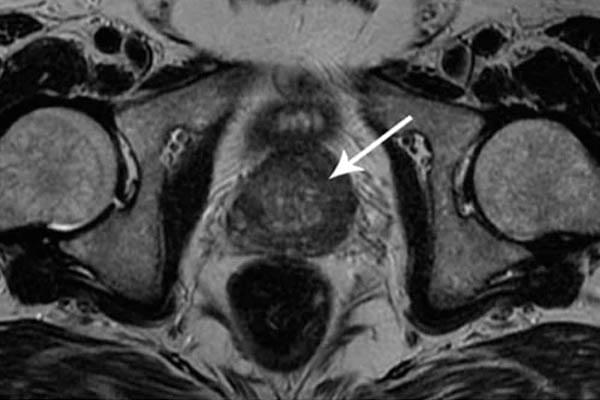

Saya ingin menunjukkan beberapa foto tentang apa yang terjadi pada sistem genitourinari dan organ dalam lainnya dari seorang pria ketika dia berhenti berhubungan seks.

Klik tampilkan, hanya jika Anda telah berusia 18+ :

alt_text

Seperti inilah peradangan prostat karena stagnasi di dalamnya (dengan tidak adanya pengosongan testis, yang terjadi saat berhubungan seks). Peradangan yang berkepanjangan pertama-tama mengarah ke adenoma, dan kemudian ke kanker prostat (dari mana, menurut statistik, 38% pria meninggal). Dengan tidak adanya seks, ini selalu terjadi, itulah sebabnya adenoma dianggap sebagai penyakit orang tua.